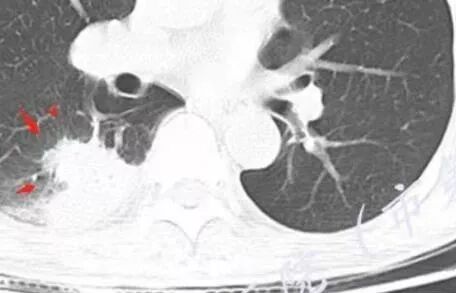

胸部CT:右肺下叶背段实变,广基底,糊墙,长轴与胸膜平行,周围晕,支气管进入堵塞,纵隔窗可见低密度坏死,实变内小空洞?脑部不会看。

胸CT:右肺下叶背段实变影,内可见小空泡,病灶与胸膜呈宽基底,实变病灶周围存在毛玻璃影,纵隔窗可见病灶内存在低密度,增强可见病灶强化,并见病灶内低密度区。头MRI不会看。

右肺下叶背段实变,广基底,糊墙,长轴与平行胸膜,周围有晕,支气管进入堵塞,可见低密度坏死及小空泡。颅内多发环形强化灶,符合脑脓肿三层结构,结合临床,考虑:感染性病变,隐球菌?鉴别肺克。

蔡磊:

肺部病灶有收缩性,支持感染性病变,但是患者病程不急,不支持肺克

右肺下叶大片实变

我们回头看肺内的,病灶位于下叶背段,可惜没重建

近肺门区见一坏死腔,内壁较清楚,空泡在周围

局部部分边缘膨隆,欠光滑

不是单纯的近端堵塞,远端不张,远端实变,宽基底

远端实变区膨隆,部分似有栽赃的趋势

感染一定有,但是应该还有警惕癌

南边:

一般来说炎性空洞坏死,空洞偏内的结核多,癌性空洞一般是远端的缺血坏死,这个病例特殊,近端支气管显示不清,内壁部分清晰,部分不清晰,是不是层厚的问题?

炎性有。从总体来说,病变分两部分,靠肺门这里是一个弧形的。从影像来说,确实有些壁不是很清楚,层厚、窗宽窗位影响,这个壁细节显示不是那么清楚。大点病灶是一个有分叶的,宽基底在外侧,病灶边缘有膨隆的迹象。

少量积液反衬外壁更好看,靠近胸膜侧有很多积液不连续,断掉,局部膨隆在外面。很大一部分是连续的,但有些部分是不连续的。有膨隆我就很难判断,病灶的膨隆是张力引起的,还是远端栽赃引起的?局部的胸膜有变化的。所以我怀疑有栽赃的趋势,为什么说趋势,是因为没看到外面一个侵犯的迹象,但是层厚原因我有些地方我不敢说,有没有侵犯。

你看我标的这个地方,我就觉得这个病灶有侵犯性,附近旁边都有一个低密度线影,局部就没了,病灶似乎直接到个肋骨的胸膜脂肪间隙下,这些地方都有类似迹象,把它当成一个大的肿块,有分叶,近端有坏死、空洞,壁外围还有有些毛糙,腔内也有些索条影。颅脑内像个转移瘤的特点,转移瘤,淋巴瘤,脓肿?脓肿腔内脓液粘稠,弥散受限,这个腔内DWI不高,这个让我犹豫.按理脓肿也要考虑.

2.影像右肺下叶大片高密度影,整体边界模糊柔和,中央见圆形液化区及微小气泡影,内壁相当光整,环形强化,未见明确壁结节。双肺门及纵隔未见增大淋巴结。这样的病灶更符合细菌性肺脓肿,以肺炎克雷伯杆菌感染最为常见。